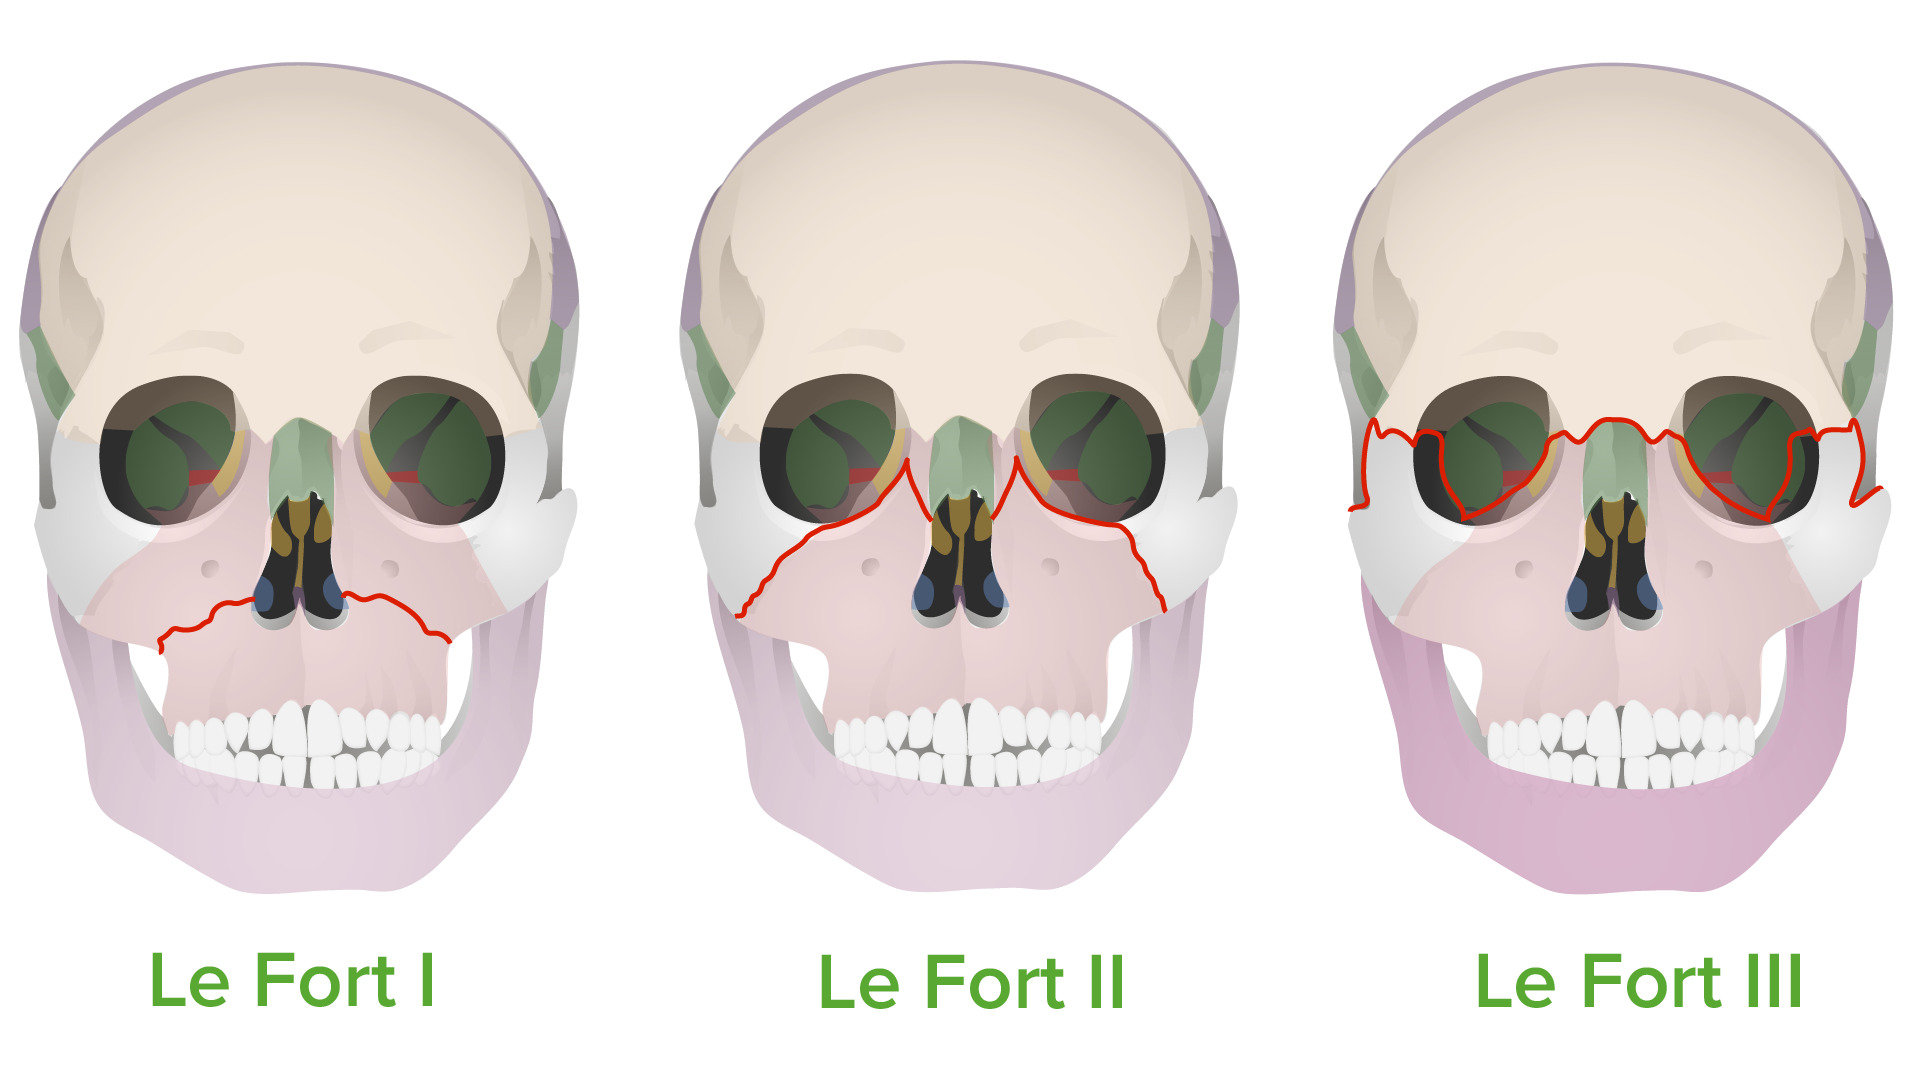

Oh shit nevermind just get LefortView attachment 4693687